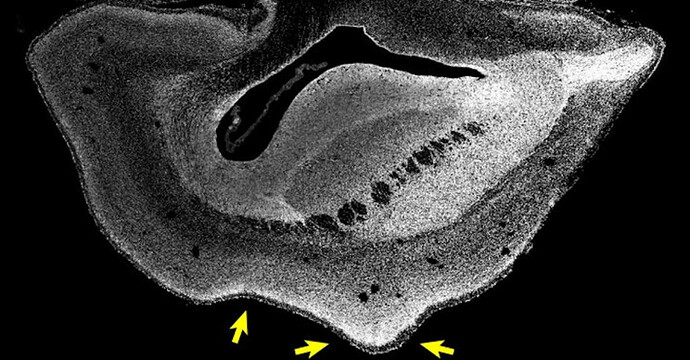

Growing monkey fetus brain, Source : Heide et al./MPI-CBG

The left-hand fetus brain is normal, and the right-hand one is the enlargened human gene monkey brain, Source : Heide et al./MPI-CBG